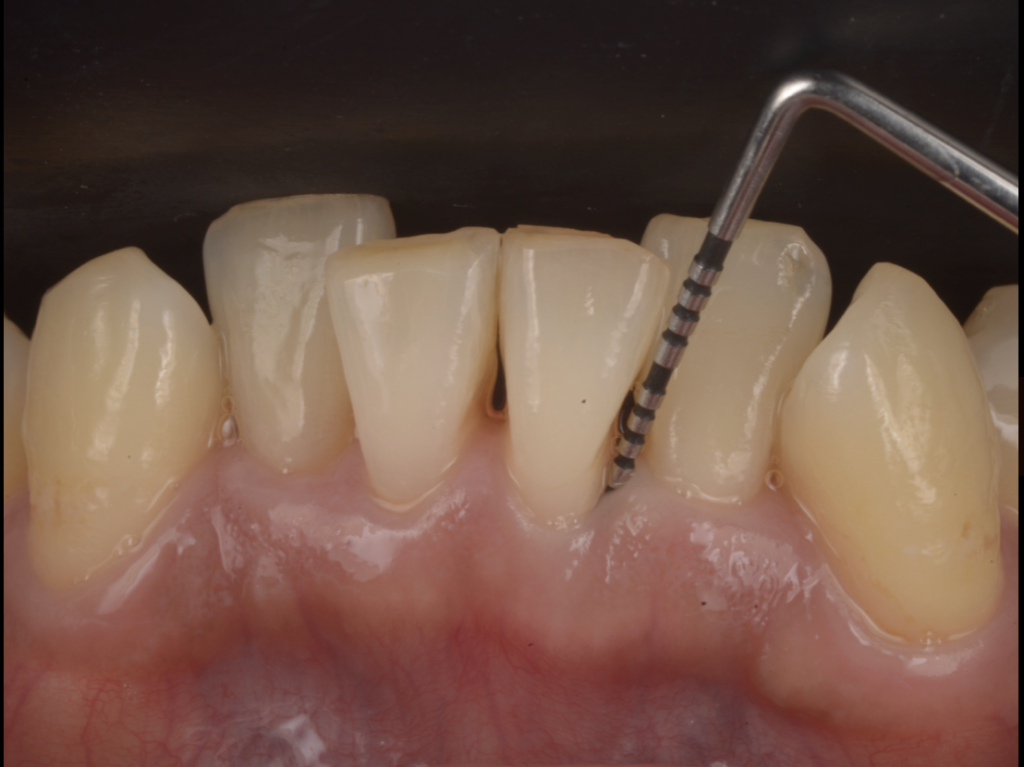

マイクロスコープとレントゲンで詳しく検査すると、

問題の歯の周囲だけ、縦に深い骨の欠損(骨吸収)があり、歯周ポケットも深い状態でした。

いわゆる“局所的に進行した歯周病”です。